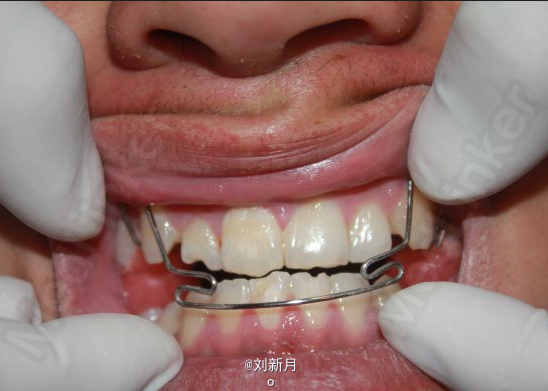

诊断:安氏III类错合 矫治计划 1.前期活动矫治,后期MBT矫治技术 2.非拔牙矫治 3.利用低位唇弓解除反合,后期排齐整平牙列 4.矫治结束后尖牙,磨牙,覆合覆盖基本正常 5.面型有所改善